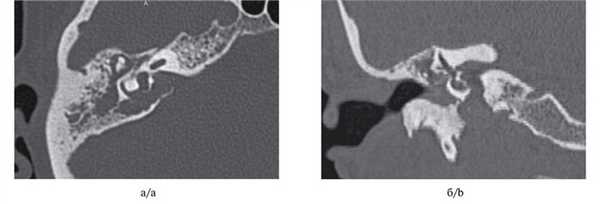

МСКТ височной кости — КТ-картина образования пирамиды правой височной кости с костно-деструктивными изменениями, правостороннего среднего отита. Образование на МСКТ височной кости отграничено сверху базальным завитком улитки и преддверием, снизу — яремной веной, медиально — твердой мозговой оболочкой задней черепной ямки, латерально — гипо- и мезотимпанумом, спереди — вертикальной частью внутренней сонной артерии, сзади — сагиттальным ПК, внутренним слуховым проходом (рис. 1). Рис. 1. МСКТ височной кости (правое ухо). КТ-картина инфралабиринтной холестеатомы пирамиды височной кости (а — аксиальная проекция, б — коронарная проекция).